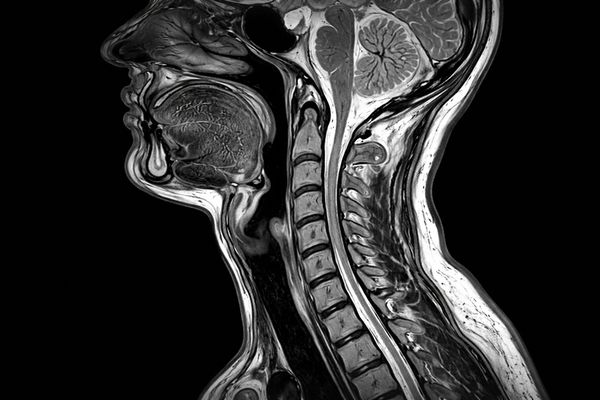

МРТ мягких тканей шеи — это неинвазивный метод визуализации, основанный на регистрации отклика тканей организма на воздействие магнитного поля. Исследование обеспечивает получение высококонтрастных послойных изображений без применения рентгеновского излучения.

Метод особенно ценен при оценке анатомически сложной области, где сосредоточены сосуды, нервные стволы, лимфатическая система и мышечные структуры.

МРТ мягких тканей шеи позволяет детально оценить состояние мышц, фасций, связочного аппарата и подкожно-жировой клетчатки.

Метод выявляет новообразования, кисты, инфильтраты, абсцессы, патологические изменения лимфатических узлов, а также поражения нервных структур и сосудистые нарушения. Высокая чувствительность исследования обеспечивает раннюю диагностику заболеваний.